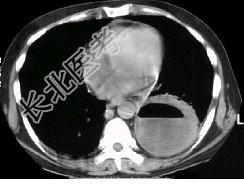

- 单项选择题男,36岁, 胸痛半月伴发高热,胸片发现占位性病变, CT检查如图,最可能的诊断为 ( )

A、左下肺肺脓肿

B、左下肺癌并空洞形成

C、左侧胸腔积脓

D、左下肺囊肿

E、左下肺肺炎